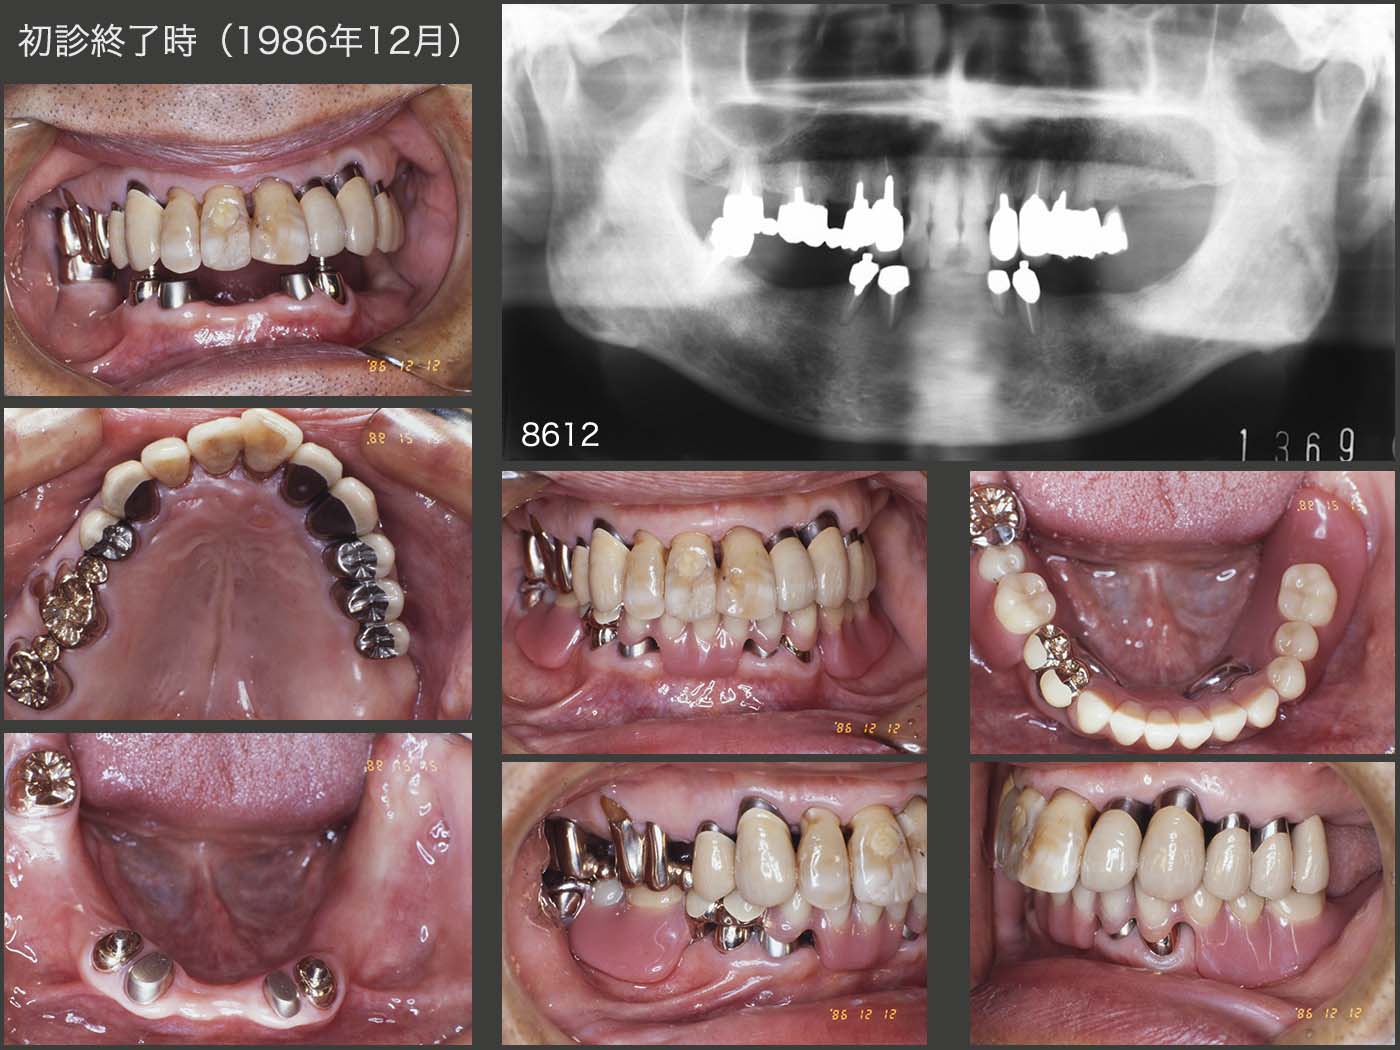

1986年12月,初診終了時の状態である.左上④⑤6には延長ブリッジを装着した.また,右上のクラウンは連結せずに単独で製作したことは,対合が義歯であることを考えれば,妥当な処置であった.右下4および左下3には,Baer stepped anchorアタッチメントを装着した.

ここで,初診からの治療を振り返ってみる.初診から9ヵ月経って,やっと下顎に暫間義歯を装着することになった.(9ヵ月も患者さんに不自由な食生活を強いてしまい本当に申し訳ない.)なお,右下4および左下3には暫間のOPAアタッチメントを仮着した.この際,右下7は抜髄のために咬合面の一部を削去しているのに対して,右上7は抜髄のため挺出している咬合面をすべて削去していることが判明した.本来なら,ここが唯一の咬合支持であるから,ここの咬合状態を保全したうえで,上顎暫間被覆冠および下顎暫間義歯の製作を行わなければならないはずである.今となっては確認できないが,右上7を削去した分,下顎位が若干低下している可能性があるかもしれない.

暫間の補綴装置を装着し,特に問題がみられなかったことから,最終補綴装置の製作にとりかかった.まず,上顎の補綴装置を先行した.つぎに,右下7のクラウンを製作するに当たって,暫間義歯を装着した状態で印象採得することで,咬合採得も同時に行った.再三述べているように,右側の上下7の咬合が下顎位の決定にとって重要である.

さらに,下顎の最終義歯を製作するに当たって,今回も暫間義歯を治療用義歯として応用した.なお,その前に暫間アタッチメントを最終アタッチメントに変更した.